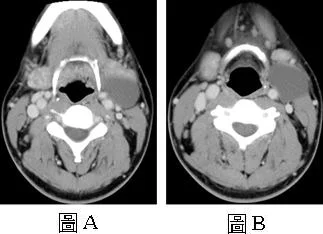

這題的解題核心在於辨識頸部囊腫的影像特徵與典型位置,圖片中左側頸部可見一個邊緣清晰、內部均勻低密度且有薄壁強化的囊狀病灶,其位置符合第二腮裂囊腫的典型表現。